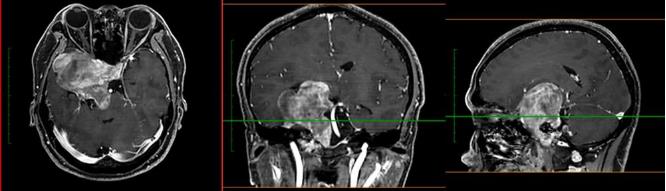

當地醫院對小成頭顱進行MRI檢查,提示:鞍區、中顱窩及后顱窩巨大占位,腦干受壓明顯,且部分已侵襲突破顱底骨質,腫瘤大小約8.2*7.3*5.8cm,此外,電子視野檢查發現右眼鼻側視野、左眼顳側視野嚴重缺損。

神經外科濮春華主任醫師和團隊在顯微鏡下嫻熟地操作,11個小時后, “盤踞”在中顱窩處的腫瘤被近全切除,一個月后,殘余在后顱窩的腫瘤也順利被“摘除”,兩次手術總計20余小時,最終獲得成功。術后病理證實軟骨及黏液基質的腫瘤,符合軟骨肉瘤 II級。